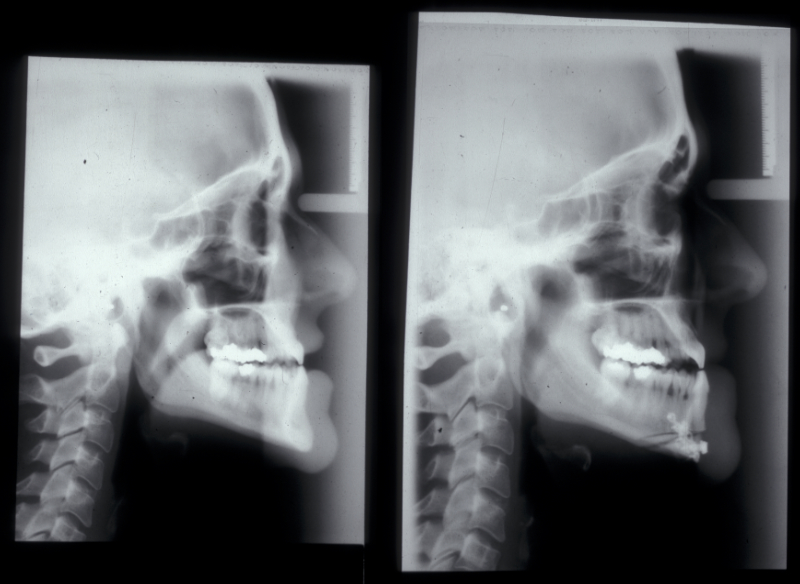

Genioplasty procedures use very similar principles to those of orthognathic procedures (Figure 10).

The chin is approached from an intraoral incision that exposes and protects the mental nerves. Bone cuts are made horizontally to retain the lingual muscle attachments. The chin is reduced by excising a middle portion of bone and inset to preserve the aesthetics of the cortical chin shape. It can be advanced by sliding forward. It is internally fixed using miniplates (Figure 11). Small asymmetries can be corrected in this way.